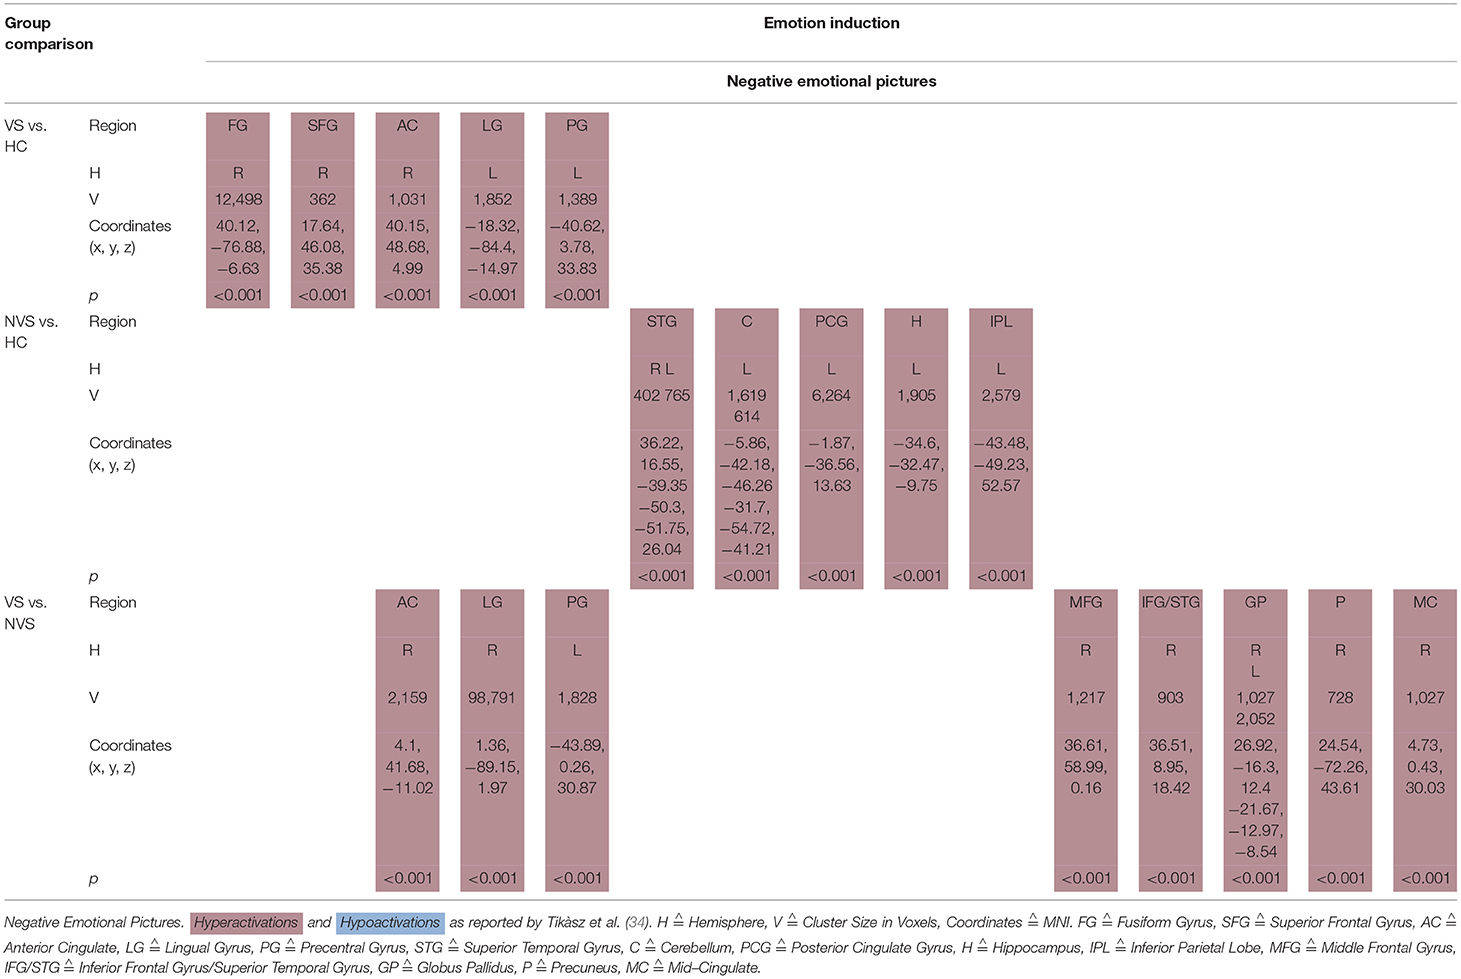

Emotional Pictures

Tikàsz et al. (34) showed negative emotional pictures to VS, NVS, and HC and observed functional alterations in brain activity (see Table 5B).

VS vs. HC hyperactivated the right fusiform gyrus, right superior frontal gyrus, right anterior cingulate, left lingual gyrus, and left precentral gyrus.

NVS vs. HC hyperactivated the superior temporal gyrus bilaterally, left cerebellum, left posterior cingulate gyrus, left hippocampus, and left inferior parietal lobe.

VS vs. NVS hyperactivated right anterior cingulate, right lingual gyrus, left precentral gyrus, right middle frontal gyrus, right inferior frontal gyrus, and superior temporal gyrus, globus pallidus bilaterally, right precuneus, and right mid-cingulate.

Negative Emotional Pictures

Tikàsz et al. (34) compared violent schizophrenia with HC and observed significant hyperactivations as response to negative emotional pictures in the right fusiform gyrus, right superior frontal gyrus, right anterior cingulate, left lingual gyrus, and left precentral gyrus.

When comparing non-violent persons with schizophrenia with HC, non-violent persons with schizophrenia showed significantly higher activation in superior temporal gyrus bilaterally, left cerebellum, left posterior cingulate gyrus, left hippocampus, and left inferior parietal lobe. A previous meta-analysis had found no differences in amygdala activations between HC and persons with schizophrenia when exposed to aversive emotional stimuli (63).

Violent as opposed to non-violent persons with schizophrenia showed hyperactivations in response to negative emotional pictures in the right anterior cingulate, right lingual gyrus, left precentral gyrus, right middle frontal gyrus, right inferior frontal gyrus and superior temporal gyrus, globus pallidus bilaterally, right precuneus, and right mid-cingulate.

Tikàsz et al. (34) discussed the increase of the anterior cingulate reactivity to negative stimuli in the violent schizophrenia group as the most important finding. Some authors suggest that the anterior cingulate is crucial for the integration of negative affect and cognitive control (64–66). It is also associated with the generation and regulation of emotion (67) and, due to connections of the anterior cingulate with both the amygdala and the orbitofrontal cortex, the anterior cingulate seems to be critically involved in violent behavior (68). Tikàsz et al. (34) conclude that anterior cingulate dysfunctions are associated with negative stimuli processing in violent persons with schizophrenia and reason that negative emotions may be a factor in preceding violent behavior.